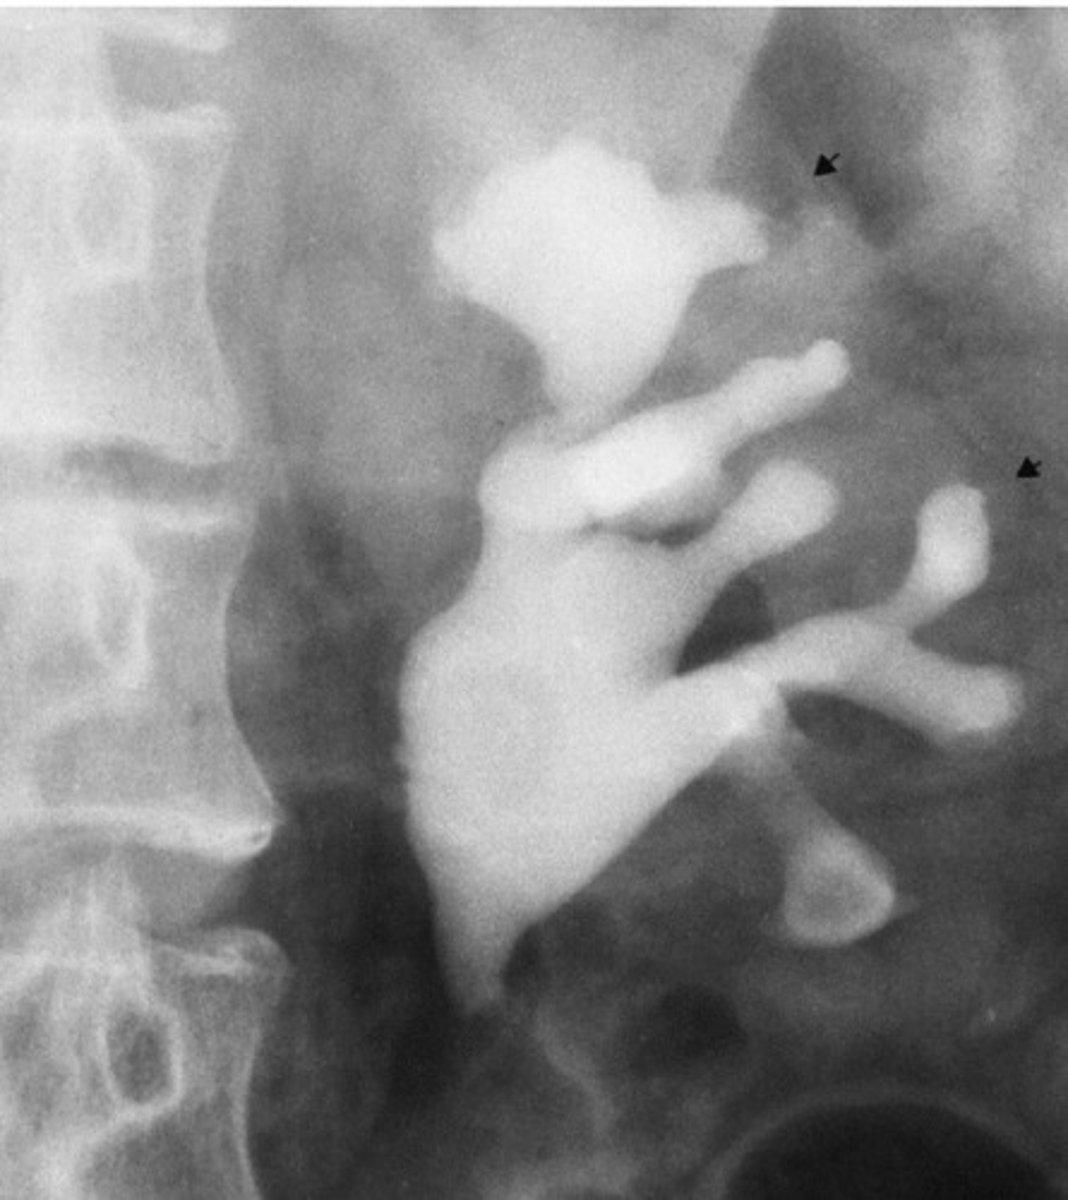

- Malrotation

- Distorted

- What congenital anomaly refers to the kidney being rotated?

- How does this pathology appear radiographically?